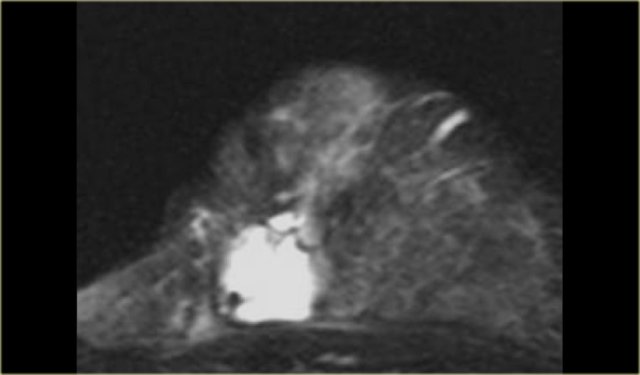

The image on the far left is of a diffuse invasive lobular carcinoma.

On the right is a MIP showing a large area of abnormal enhancement, which proved to be a diffuse invasive lobular carcinoma.